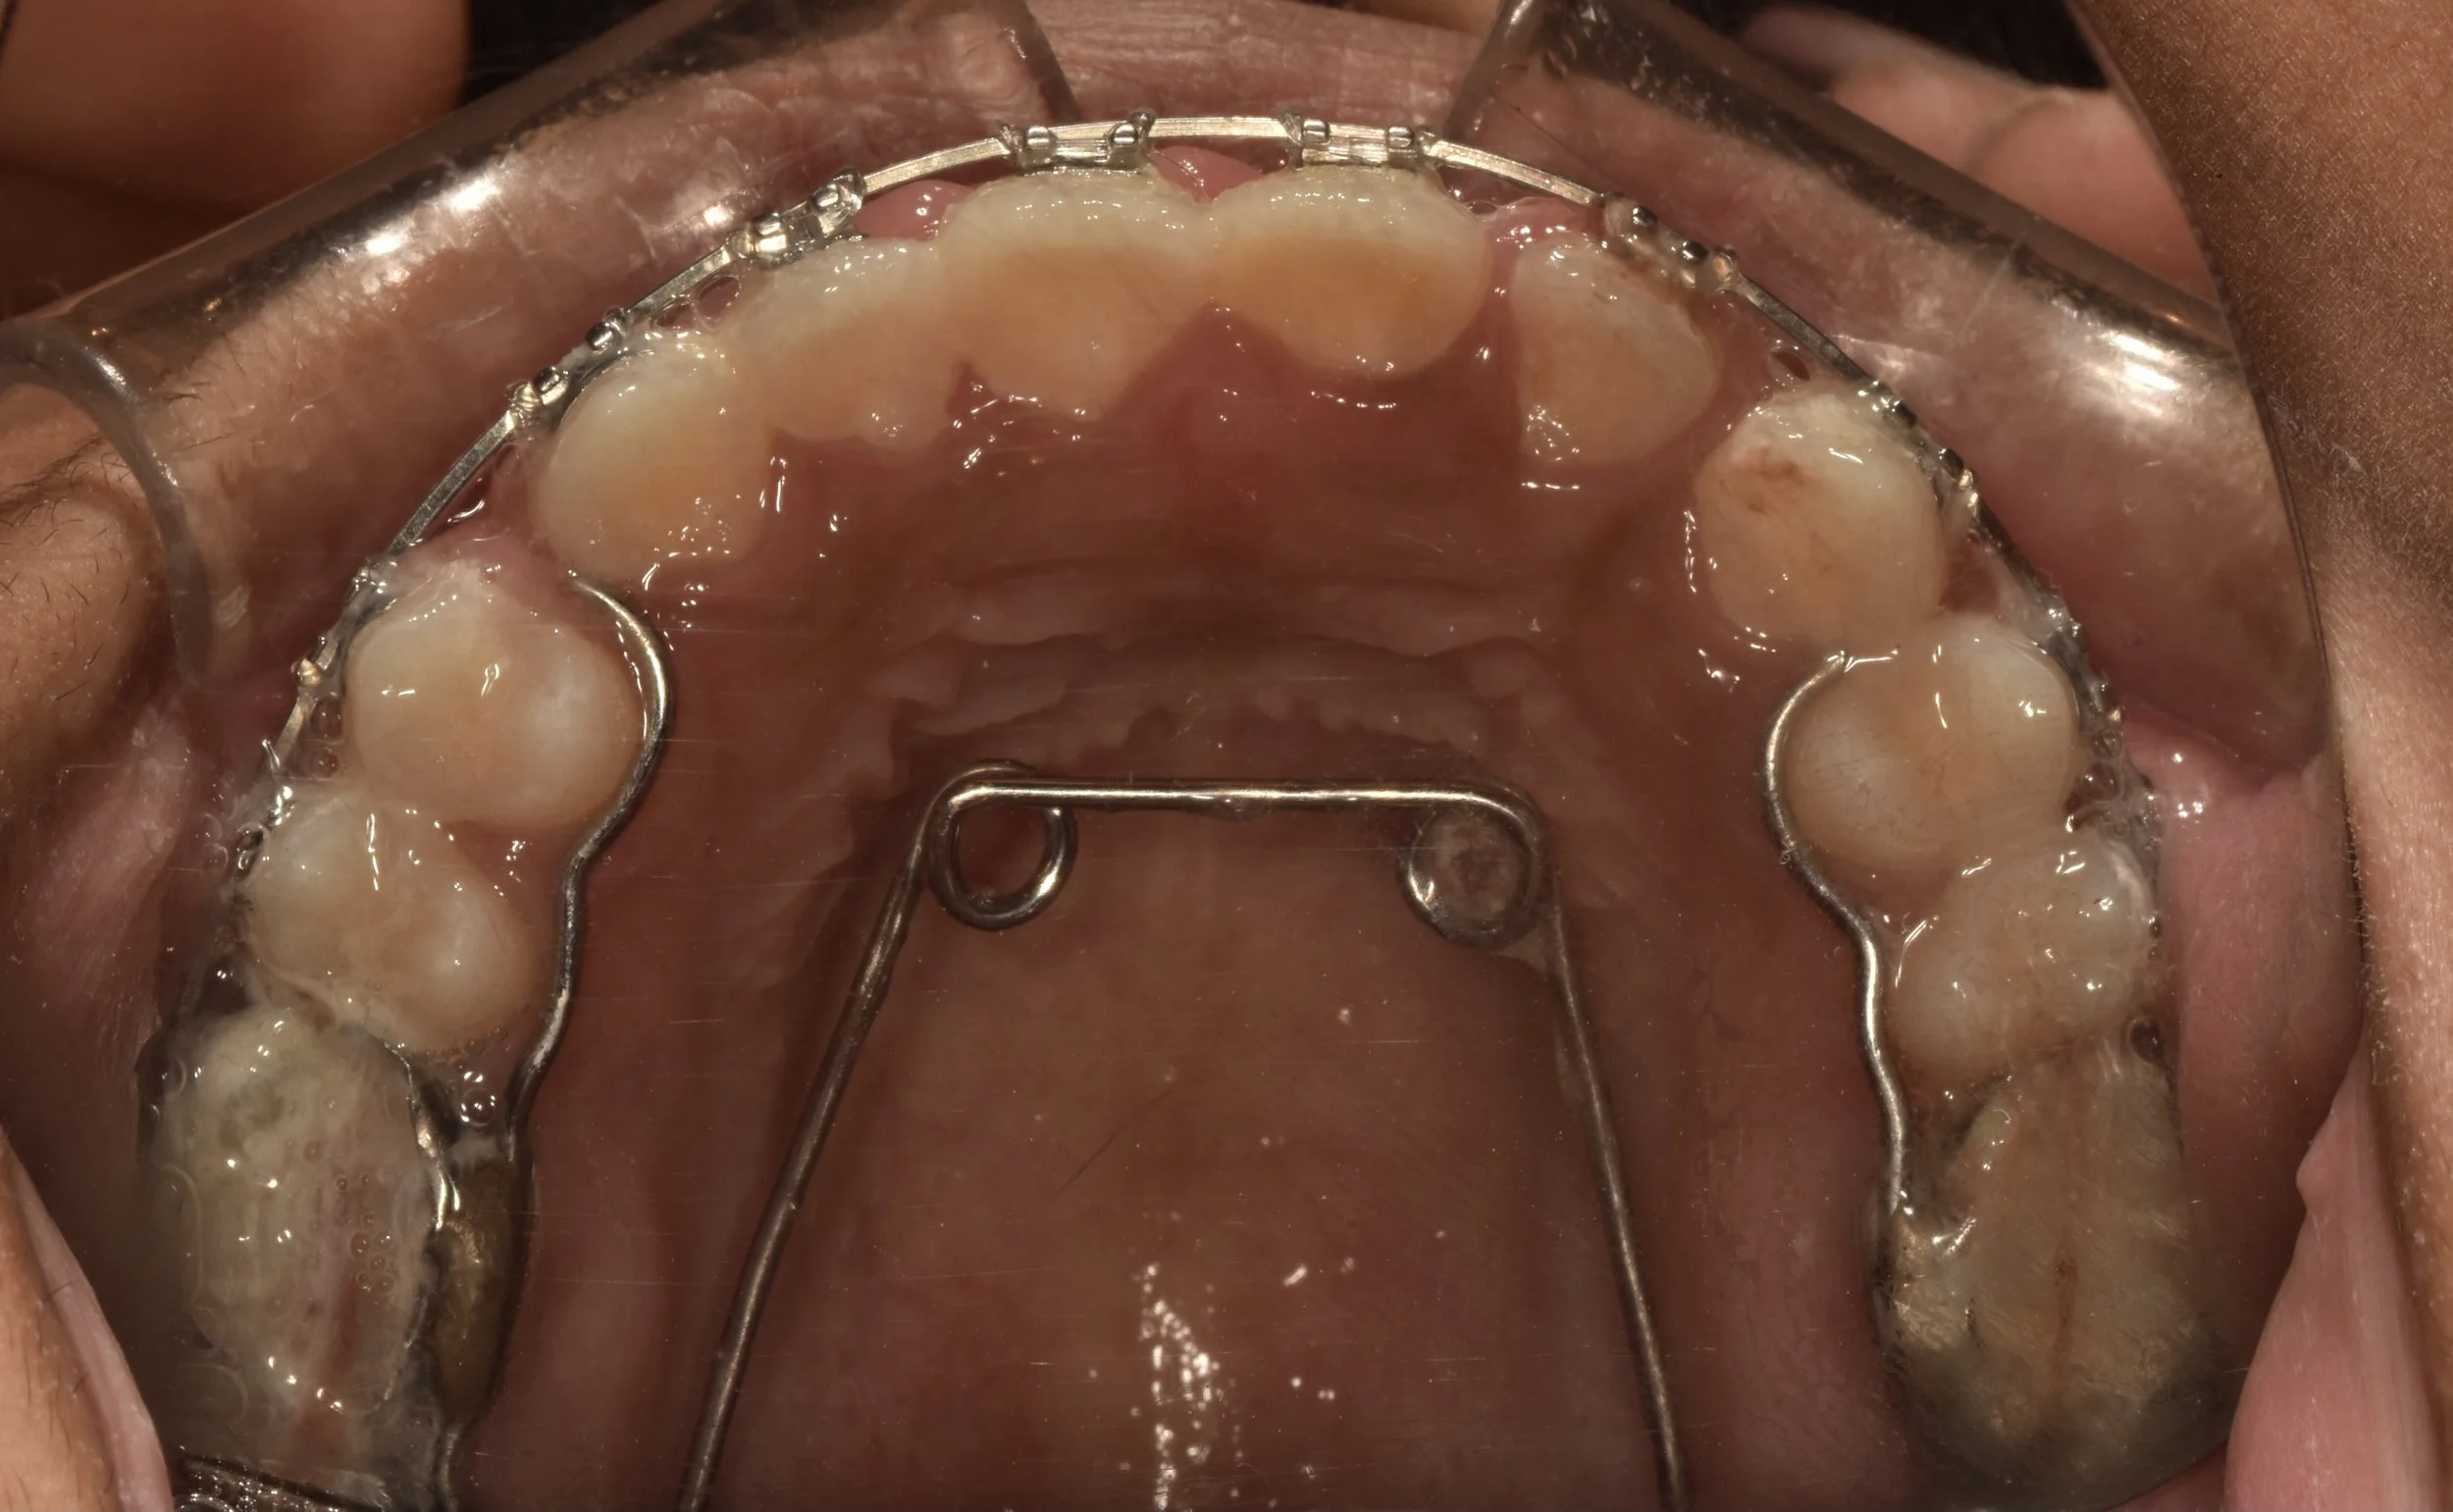

ARCH EXPANSION - ATTEMPTING NON-EXTRACTION ORTHODONTICS

ARCH EXPANSION - ATTEMPTING NON-EXTRACTION ORTHODONTICS

MINI-IMPLANT PLACEMENT

MINI-IMPLANT PLACEMENT

MINI-IMPLANT PLACEMENT

Mini-implants are small diameter implants screwed into bone to gain maximum anchorage to perform various tooth movements. Its not as complex as u think! its a relatively the most simplest and economic way to achieve maximum strength. Its easier to place and to remove chair side requiring hardly 3-5 minutes.